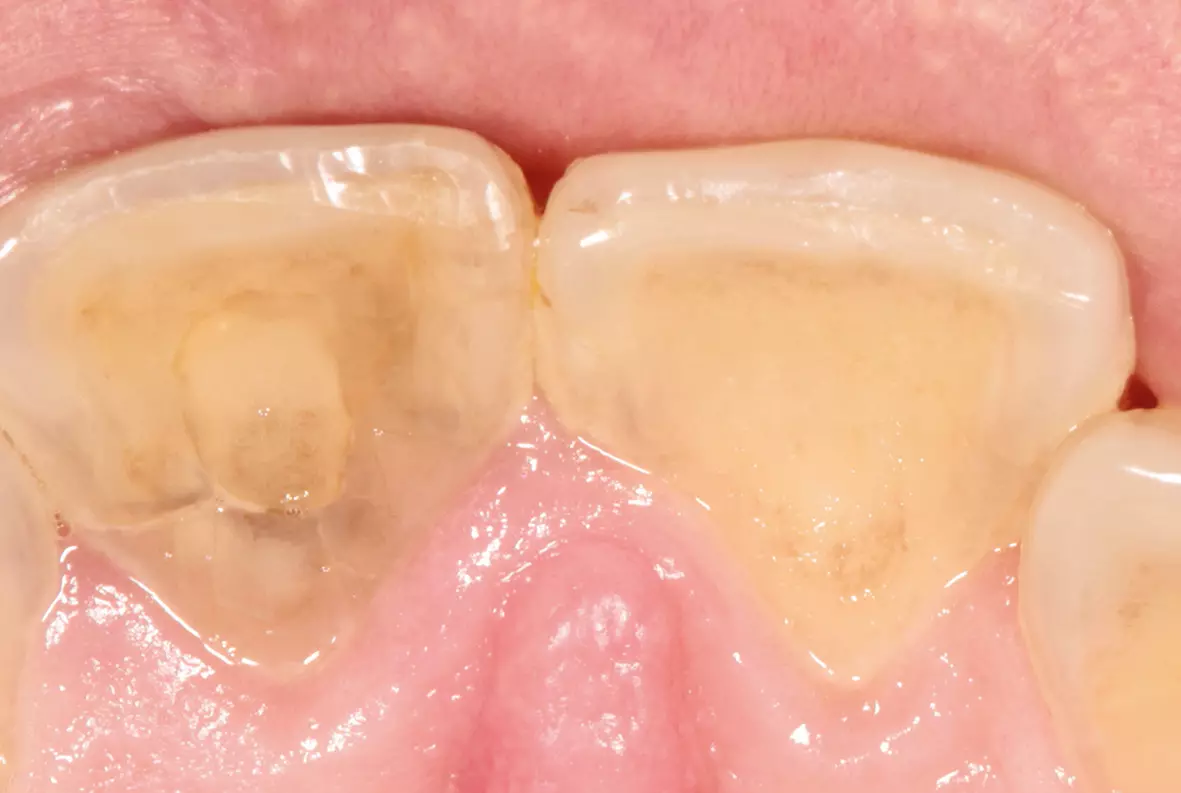

Bei dem Patienten wurde bei Zahn 11 eine Querfraktur festgestellt. Leider konnte der Zahn nicht mit konservierenden Maßnahmen erhalten werden und es stand eine Extraktion an. Das weitere Vorgehen wurde mit dem Zahntechnischen Labor abgesprochen. Mit Hilfe der Situationsmodelle konnte zunächst ein Provisorium erstellt werden. Nach der Extraktion des Zahnes wurde die Socket Preservation Technik unter Verwendung von Bio-Oss® Collagen von Geistlich Biomaterials und einem Schleimhauttransplantat vom Gaumen angewandt. Es konnte eine provisorische Schiene zum Ersatz von Zahn 11 eingesetzt werden (Abb. 4).

Durch den Aufbau des räumlich korrekten Knochenvolumens konnte bei der Implantatplatzierung die ursprüngliche Situation wiederhergestellt werden. Als „Wax-up“ diente der extrahierte Zahn (Abb. 11). So konnte jetzt entweder gleich die definitive Krone oder eine provisorische Krone hergestellt werden. Wir entschieden uns für die Herstellung einer provisorischen Krone, um die Reaktion der Gingiva auf die Implantatkrone zu beobachten und gegebenenfalls noch darauf reagieren zu können (Abb. 12 bis 14).